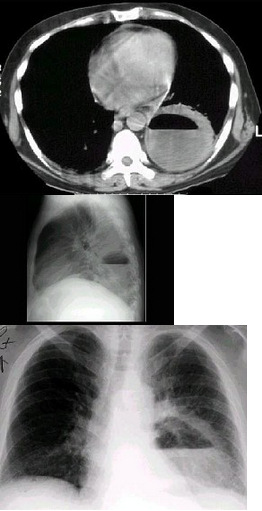

11、单项选择题

女,40岁,高热伴胸痛1周,CT如图,最可能的诊断是()

A.支气管囊肿

B.淋巴瘤

C.纵隔脓肿伴淋巴结反应性肿大

D.胸腺囊肿

E.恶性畸胎瘤